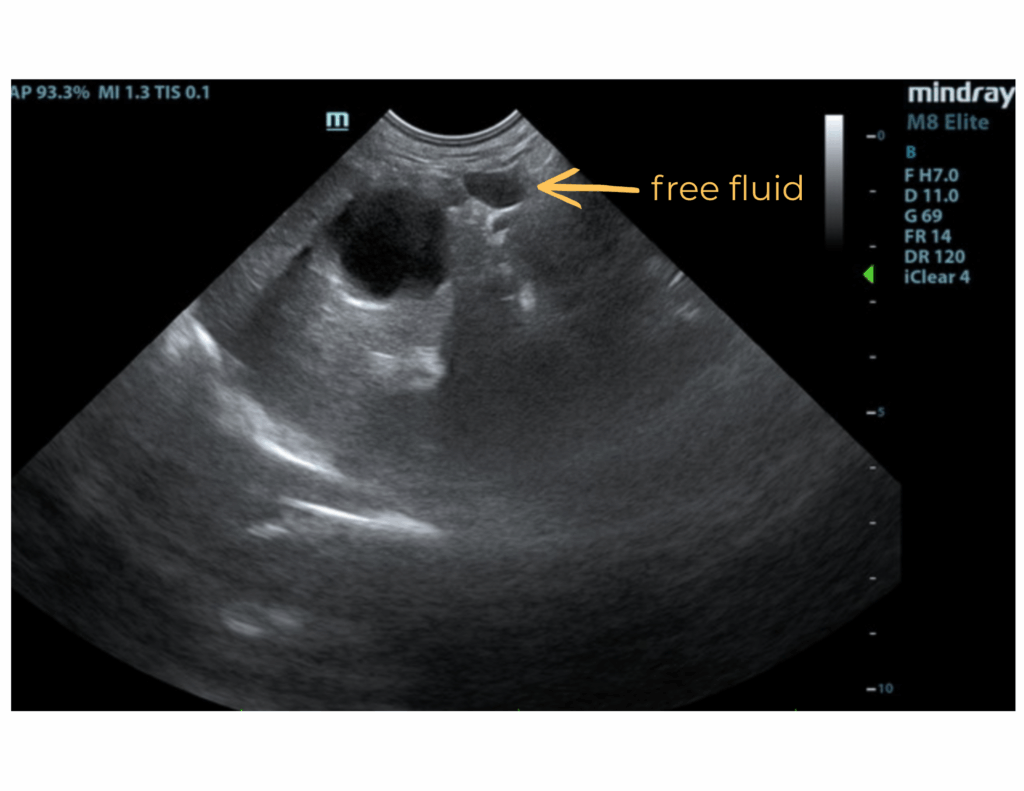

Free Abdomen:

A slight amount of free fluid was noted.

- Splenic mass.

- Free fluid.